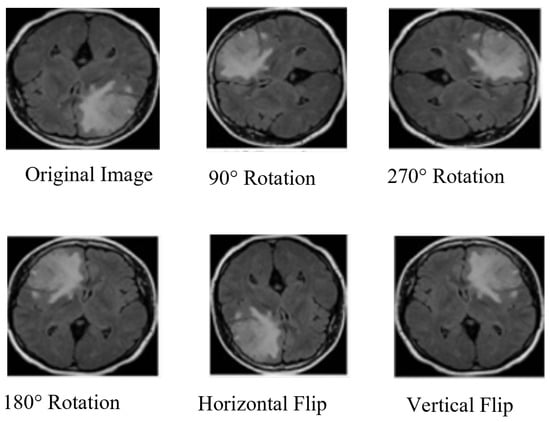

3.3. Data Augmentation

| Parameters | Values |

|---|---|

| Horizontal flip | True |

| Vertical flip | True |

| Range scale | True |

| Zoom range | [0.1, 1.0] |

| Width shift range | 0.2 |

| Height shift range | 0.2 |

| Shear range | 0.2 |

| Brightness range | [0.2, 1.0] |

| Random rotation | [0–90] |